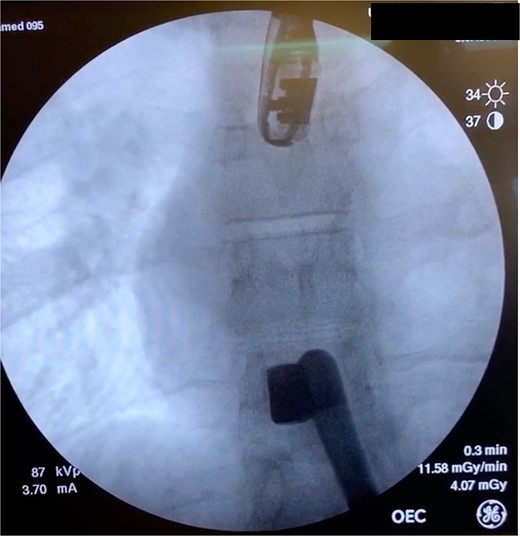

In the OR, exploratory laparotomy, right nephrectomy, liver packing, and pericardial window were performed. The pericardial window was negative for blood. With no suspected cardiac injury, intraoperative fluoroscopy (Fig. 1) and transesophageal echocardiogram (TEE) (Fig. 2) were used to locate the bullet. It was suspected to be intravascular secondary to venous embolism from the retro-hepatic inferior vena cava (IVC). Cardiothoracic surgery was consulted for removal of the bullet. With abdominal hemorrhage controlled, the surgeons agreed the patient was an acceptable risk for anticoagulation and cardiopulmonary bypass. Sternotomy was performed, the patient was placed on cardiopulmonary bypass, and the bullet was removed through a right atriotomy.

Intraoperative TEE demonstrating the intravascular bullet in the IVC.

Case 1 involved a stable patient with a single GSW to the left back and a retained bullet over the right ventricle. The trauma team identified the bullet overlying the cardiac silhouette and performed a CT scan to determine its trajectory. The scatter artifact complicated localization, but a pericardial window excluded cardiac injury. Intraoperative imaging (fluoroscopy and TEE) revealed a venous bullet embolism from the retro-hepatic IVC to the right ventricle. The bullet was mobile on fluoroscopy, and TEE provided the best imaging. The trauma and cardiothoracic surgeons discussed bullet removal timing, considering the patient’s stability and heparinization needs. They opted for immediate removal due to the potential lethality of pulmonary artery embolism. The operation was successful, requiring only one surgery for definitive management. This case highlights the success of immediate bullet removal in hemodynamically stable, asymptomatic patients with venous embolism.